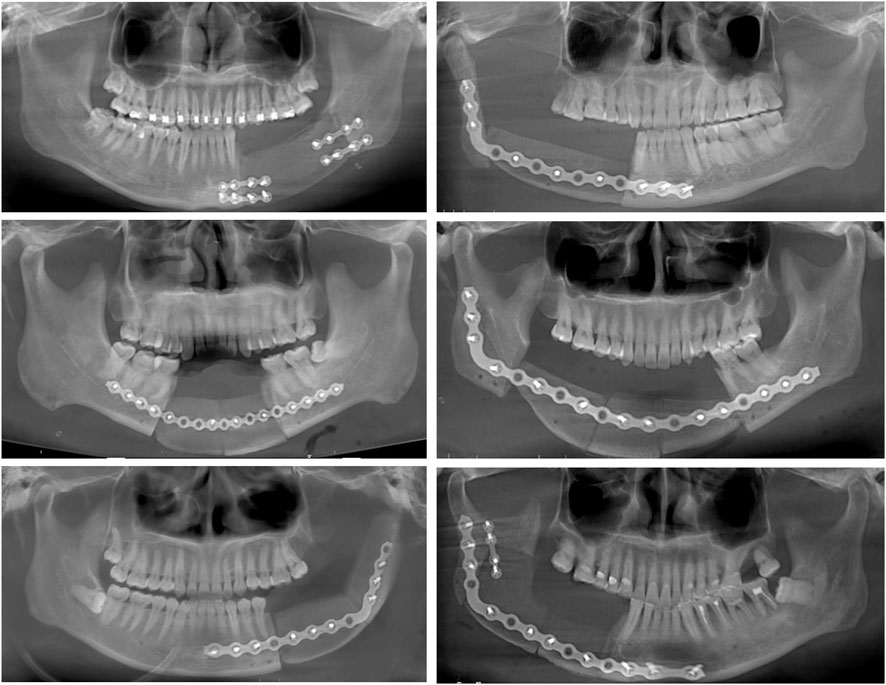

Can Titanium Miniplates Provide Superior Fixation Compared to Reconstruction Plates in Mandibular Repair with Iliac Crest Flaps? : A Retrospective Study

This study retrospectively analyzed 112 patients who underwent mandibular reconstruction with vascularized iliac crest flaps using different fixation strategies in routine clinical practice. Under comparable defect lengths and heights, reconstruction using mini plates was associated with the shortest operative time (p < 0.001), while postoperative drainage duration showed no significant difference among groups (p = 0.958). The number of iliac bone segments varied significantly among fixation methods: reconstruction plates (alone or combined with mini plates) were predominantly applied in multi-segmental reconstructions, whereas mini plates were mainly used for single-segmental repairs. Postoperative quality of life was evaluated using the University of Washington Quality of Life Questionnaire (UW-QoL). Although the fixation methods were selected according to defect complexity and surgical requirements, all approaches achieved satisfactory outcomes, and no significant difference in overall quality-of-life scores was observed among the three groups (p = 0.354). However, a significant difference was observed in the "Swallowing" domain, with patients in the mini plate group reporting better swallowing function (p = 0.009).